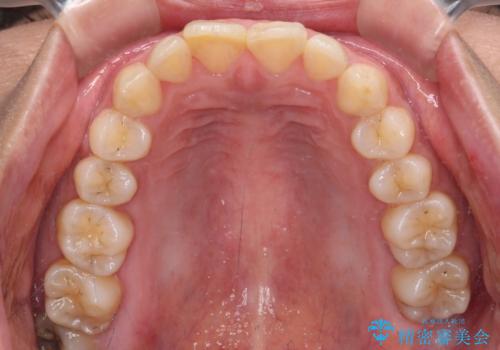

転んで欠けてしまった前歯 オーダーメイドのオールセラミッククラウン

- 転んで欠けてしまった前歯を気にして来院された患者様です。

転んだ際に歯の先端1/4ほどが欠けてしまい、近医にて修復をしてもらったとのことですが、将来的にオールセラミッククラウンを装着する可能性を説明されたため、当院にて補綴治療を行うこととしました。

オーダーメイドタイプのセラミッククラウンは、既製タイプのク色のラウン(スタンダードタイプ)とは異なり、色合いが合うまで何度も修正を行って調整をいたします。